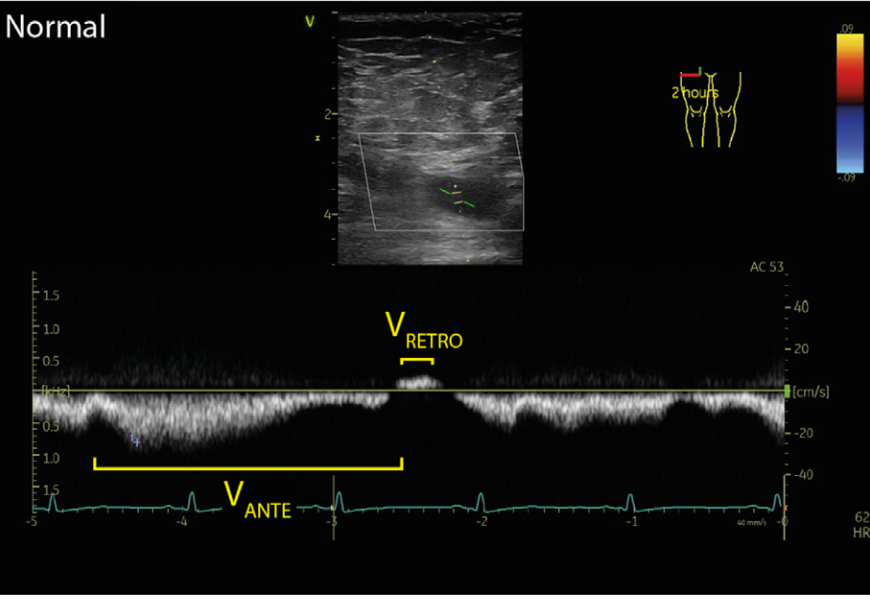

Normal femoral vein flow Doppler for comparison. Note the respiratory modulation and wide monophasic negative vein flow velocity representing antegrade vein flow with minor retrograde vein flow components.